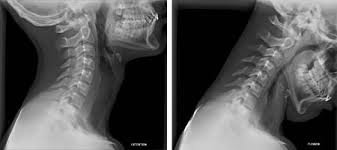

This procedure may be used to diagnose back or neck pain, fractures or broken bones, arthritis, degeneration of the disks, tumors, or other problems. Enter search terms and tap the search button. They show pictures of your internal tissues, bones, and organs. Please understand that our phone lines must be clear for urg. Here's what to expect with this painless procedure and why your dentist may recommend it.

This procedure may be used to diagnose back or neck pain, fractures or broken bones, arthritis, degeneration of the disks, tumors, or other problems. It's commonly done after someone has been in an automobile or other accident. They show pictures of your internal tissues, bones, and organs. Here's what to expect with this painless procedure and why your dentist may recommend it. Please understand that our phone lines must be clear for urg. Enter search terms and tap the search button.